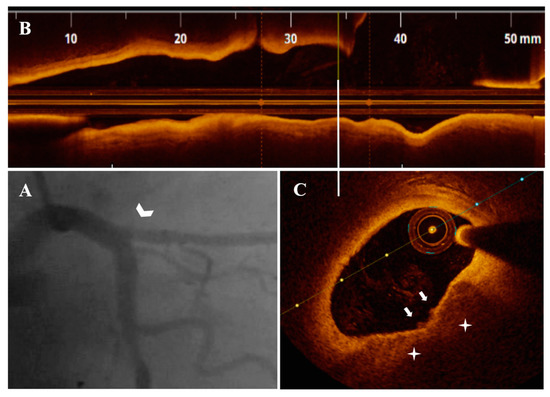

Figure 7.

A 70-year-old patient presenting with UAP. (A) CA—borderline mid-LAD stenosis (white arrowhead), significant first diagonal ostial stenosis (blue arrowhead). (B) OCT—LAD plaque longitudinal view. (a,b) Nonsignificant LAD stenosis (area stenosis = 56.5%) presenting SCP (white star) with PE and red thrombus (white arrow).